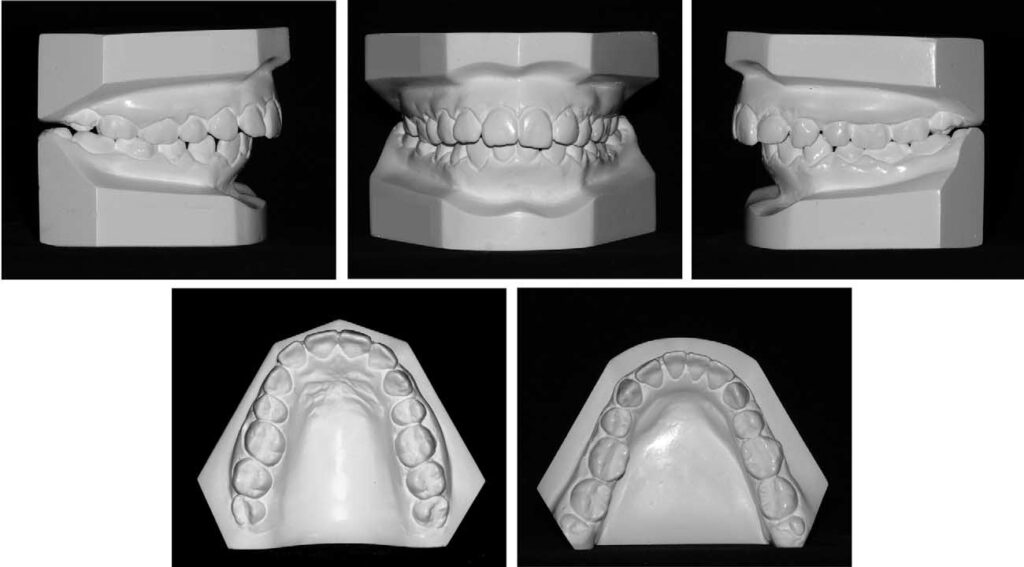

Fig 3. Study models before retreatment.

A 23-year-old woman came for orthodontic treatment to the private orthodontic office of Dr M.R.J. Her major complaint was the persisting large overjet. She was undergoing orthodontic treatment with extraction of 4 first premolars to correct a Class II Division 1 malocclusion. Unfortunately, her treatment was not proceeding well because of her lack of compliance with headgear to reinforce anchorage. As a result, despite the extractions, she still had a significant overjet (Figs 1-3). There was no crowding, and the curve of Spee was mild. Because she was not satisfied with her progress at that stage, she abandoned treatment, with the orthodontic appliances still in place. One and a half years later, she decided to continue her treatment with Dr M.R.J. Cephalometrically, there was a severe Class II skeletal relationship with compensating maxillary and mandibular incisor tipping. The soft tissue profile was convex with a retruded mandible and chin (Fig 4 and Table). However, the patient said nothing about these characteristics. Radiographically, the maxillary third molars were in a favorable position functionally, but the mandibular third molars were not. Because of the previous unsuccessful orthodontic treatment, the maxillary incisors already had significant root resorption (Fig 5). There were no signs of active periodontal disease.